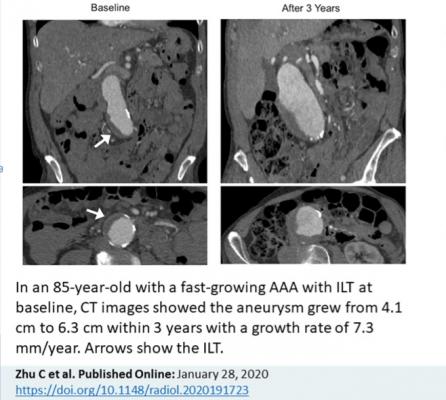

Zhu and colleagues focused their study on the intraluminal thrombus, a blood clot on the wall of the aorta at the location of the aneurysm. Intraluminal thrombi are present in the majority of aneurysms close to the repair threshold of 5.5 cm, and in a considerable number of smaller aneurysms. Despite their prevalence, the influence of these clots on abdominal aortic aneurysm growth and rupture risk is still not fully understood.

Slightly more than half of patients had an intraluminal thrombus. The aneurysms of those with intraluminal thrombus were larger at baseline and grew by a rate of 2 mm per year, twice as fast as the 1 mm per year growth rate in people without intraluminal thrombus.